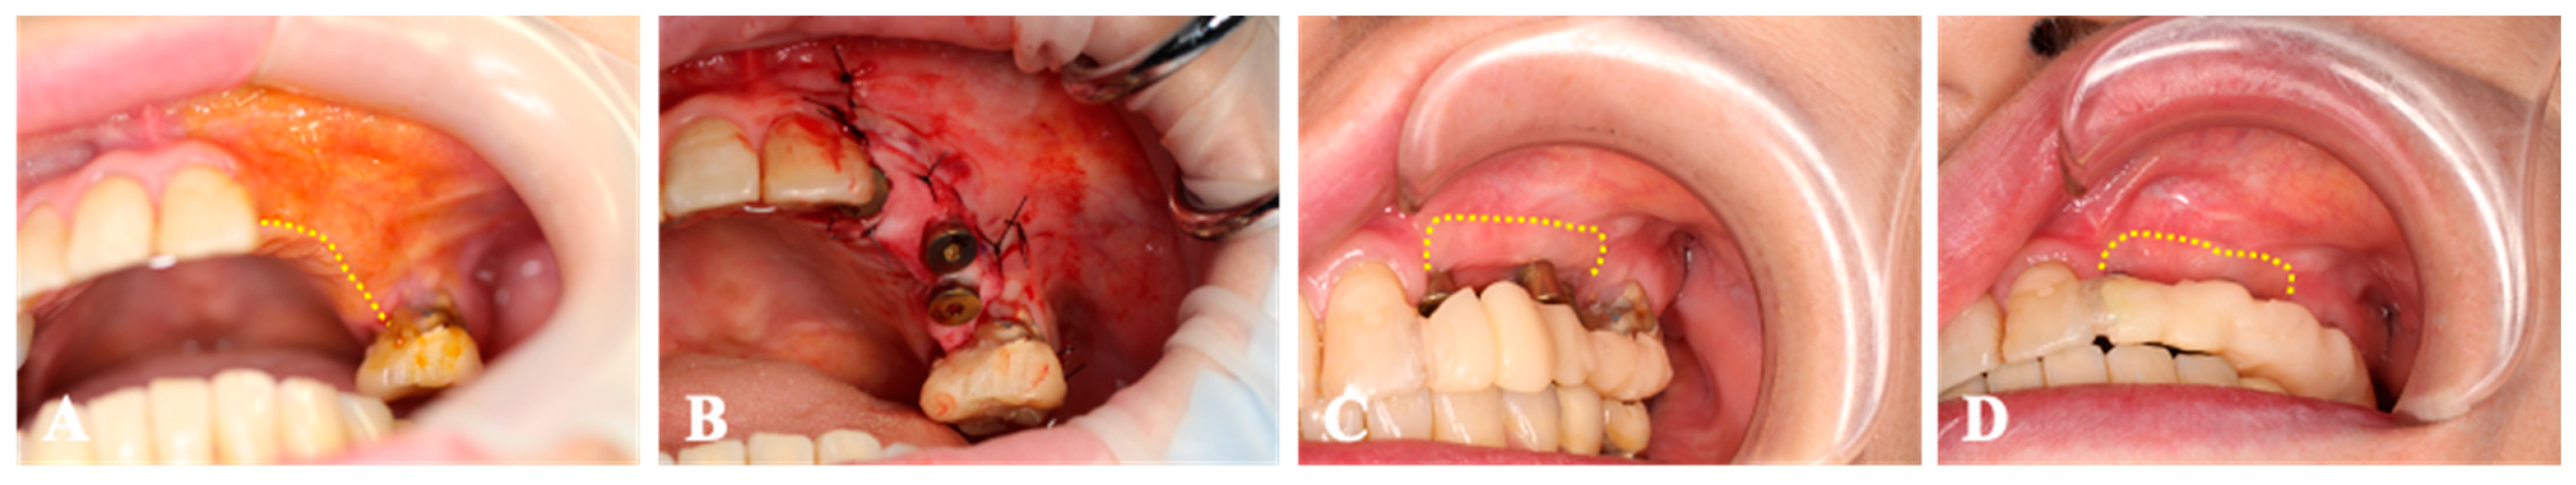

Case 1. A 67-year-old woman who had inadequate keratinized tissue band in both mandibular molar regions (Figure 4) was submitted to a one-stage implant, with the implant placed on 36, 37, 46, and 47 and a micro-graft. A piece of gingival connective tissue was harvested from the palatal mucosa of both maxillary tuberosities. The collagen sheet (size 10 × 20 mm2) with MGCTs covered the periosteum surrounding the implants. Four weeks after the surgery, there was an expanded region of peri-implant mucosa at the buccal side, and this area was maintained 2 months after transplantation. Throughout the entire period, no AEs were observed.

Figure 4.

Case 1. (A); The keratinized tissue band was located at the alveolar crest (dotted-line). (B); The collagen sheet with micronized-gingiva covers the periosteum surrounding the implants. (C); The region of peri-implant mucosa is expanded at the buccal side (dotted-line) 4 weeks after transplantation. (D); The peri-implant mucosa region maintains its area 2 months after surgery.